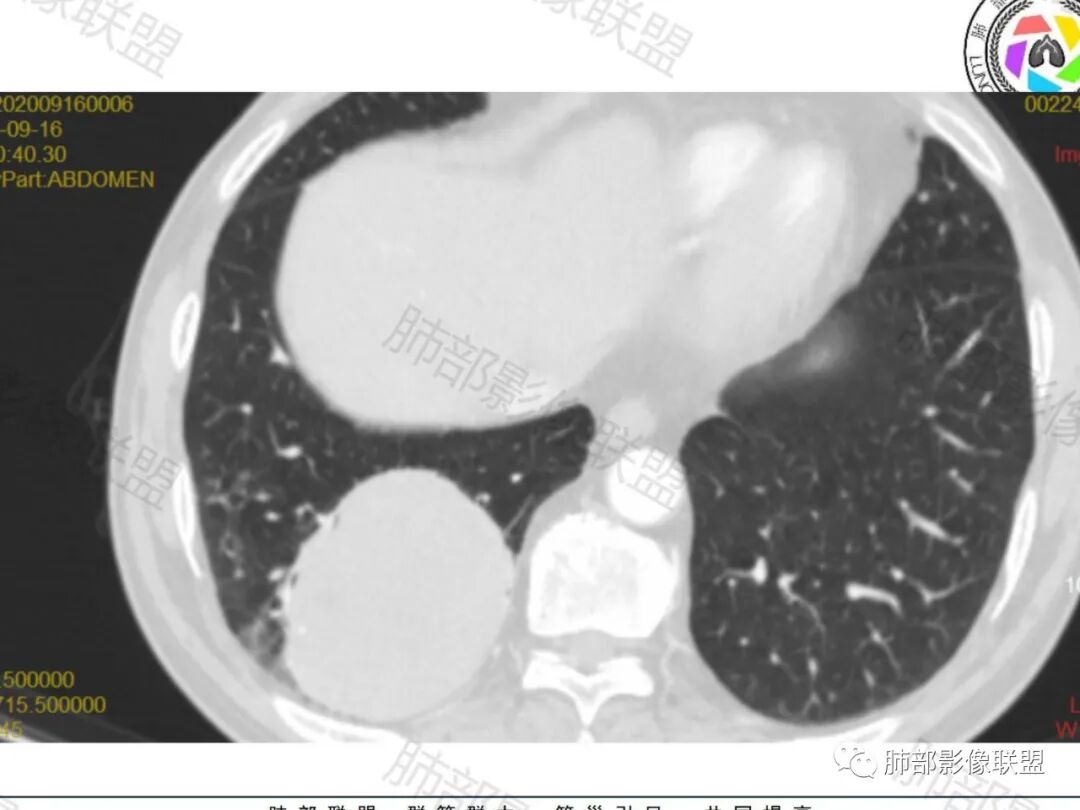

右肺下叶一类圆形肿块影,内缘边缘光滑,外缘边界模糊,可见磨玻璃影,整体以彭隆为主,部分边缘包绕支气管,平扫密度尚均匀,增强后不均匀强化,部分与膈肌黏连,临床,62岁男性,无症状,考虑恶性:腺癌,鳞癌,神经内分泌癌,肉瘤

老年人,偶然发现,右肺下叶类圆形软组织占位,密度较均匀,病灶边缘光滑,无毛刺分叶,支气管血管受挤压向外移位,增强病灶强化较均匀。考虑恶性肿瘤,外向内生长,肉瘤,肉瘤样癌,癌肉瘤,其次神经内分泌癌。

老年男性,检查发现右下肺占位。CT:右肺下叶一类圆形肿块影,膨隆,无分叶,边缘基本光滑,近端支气管推挤狭窄,与胸膜夹角为锐角,增强见不均匀强化,未见坏死,近端见血管贴边,胸壁脂肪间隙清楚。考虑良性病变——PSP可能性大。鉴别神经内分泌癌、肉瘤、SFT。

右肺下叶软组织肿块,边缘光滑,临近血管受压变形且增粗,增强后见斑片状低强化区,界不清,实性部分见条状血管影,边缘光滑,考虑PSP可能,肿块与支气管关系不密切,腺癌,腺鳞癌不符合,肿块内增强后血管走形自然,间叶组织起源肉瘤不符

右肺下叶肿块,呈外带大内带小的椭圆形改变(内带受支气管及血管挤压原因),边缘光滑,无分叶毛刺,支气管受压,增强后,均匀延迟强化,动脉期见血管贴边,静脉期内部瘤样血管强化区,相邻胸膜无侵犯,纵隔无淋巴结肿大,符合PSP,不鉴别。

胸部CT:右肺下叶一类圆形肿块影,边界清楚,大部分边缘光滑、外缘边界模糊,邻近支气管推移、血管贴边,病灶内可见分枝状血管,平扫密度尚均匀,增强后大部分均匀延迟强化,部分与膈肌黏连、尾征?考虑:类Ca>PSP>SFT。鉴别肉瘤样Ca,CD等。

肿块位于周围(起自细支气管呼吸道上皮),均匀膨胀生长(符合良性的生长特点),病灶内部大部分密度较均匀,部分小低密度不强化区(囊变),增强强化较明显,边缘血管增粗贴边,临近支气管受压,支持PSP。